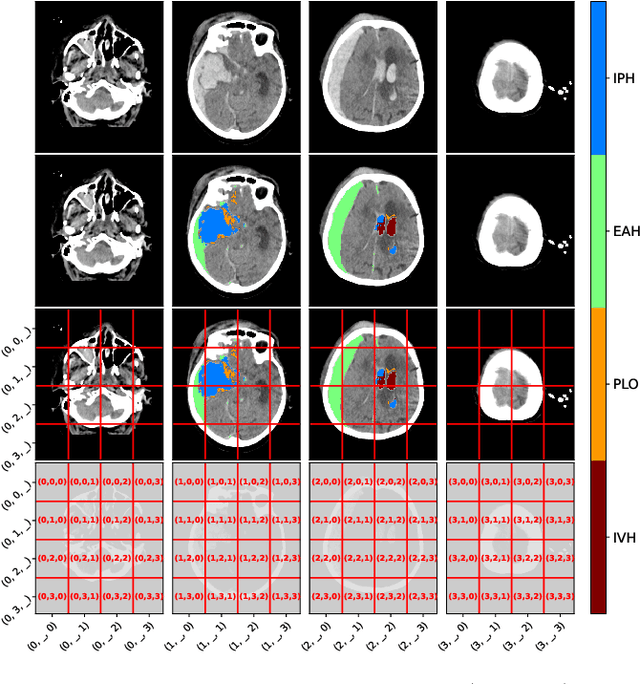

Abstract:The accurate prognosis for traumatic brain injury (TBI) patients is difficult yet essential to inform therapy, patient management, and long-term after-care. Patient characteristics such as age, motor and pupil responsiveness, hypoxia and hypotension, and radiological findings on computed tomography (CT), have been identified as important variables for TBI outcome prediction. CT is the acute imaging modality of choice in clinical practice because of its acquisition speed and widespread availability. However, this modality is mainly used for qualitative and semi-quantitative assessment, such as the Marshall scoring system, which is prone to subjectivity and human errors. This work explores the predictive power of imaging biomarkers extracted from routinely-acquired hospital admission CT scans using a state-of-the-art, deep learning TBI lesion segmentation method. We use lesion volumes and corresponding lesion statistics as inputs for an extended TBI outcome prediction model. We compare the predictive power of our proposed features to the Marshall score, independently and when paired with classic TBI biomarkers. We find that automatically extracted quantitative CT features perform similarly or better than the Marshall score in predicting unfavourable TBI outcomes. Leveraging automatic atlas alignment, we also identify frontal extra-axial lesions as important indicators of poor outcome. Our work may contribute to a better understanding of TBI, and provides new insights into how automated neuroimaging analysis can be used to improve prognostication after TBI.